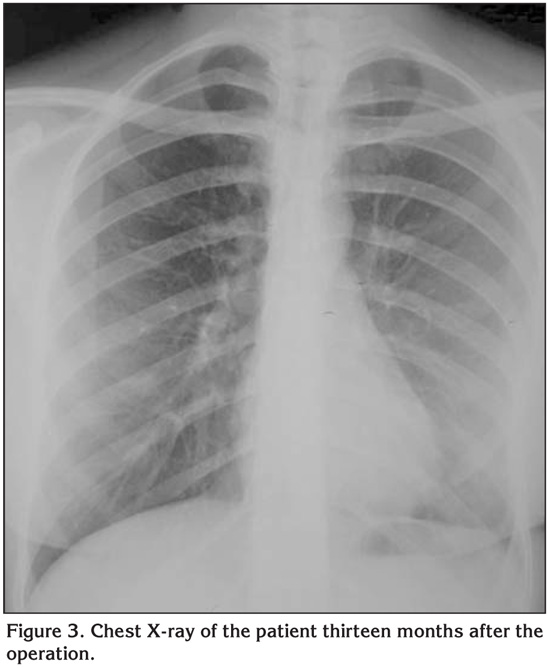

A 28-year-old woman presented with pain on her left side for three months. On physical examination, pain was present with palpation on the left side of chest wall and lung sounds were normal. Laboratory examinations were unremarkable. Postero-anterior chest X-ray showed opacity on the left sixth and seventh ribs. The patient admitted to our clinic with thorax computed tomography (CT) and PET/CT (positron emission tomography/computed tomography). CT of the thorax revealed an ill-defined destructive mass on the left anterolateral region of the sixth and seventh ribs (Figure 1). PET with 18 F-FDG depicted the lesion as a low grade malign neoplasm (SUVmax: 4.5) without any metastasis. We thought that the lesion was malignant according to the clinical and radiological findings. Because of the pain, we did not prefer taking biopsy under local anesthesia; we did it under general anesthesia. We studied frozen from the soft parts of the tissue which was taken with incisional biopsy. It was reported as malignant mesenchymal tumor or osteosarcoma. She underwent left posterolateral thoracotomy and a moderate swelling through the inside of left hemithorax originated especially from the sixth rib was detected. The sixth and the seventh ribs were enblock resected. Histopathological examination revealed the neoplastic cells that were uniformly small with diffuse growing pattern. These cells were strongly stained with focal SMA (smooth muscle actin) areas with vimentin. Tumor cells were negative for CD45, CD99, CD33 and CD56. Also chromogranin, pancreatin, EMA, TTF-1 were all negative. In addition to these findings, the most important component was osteoid production especially on the invaded regions (Figure 2). According to these clinical and histopathological findings the case was reported as primary SCO of the ribs. She was discharged on the 7th day of operation without any complication and referred to the medical oncology unit for chemotherapy. She was healthy and disease-free on the 17th month of follow-up (Figure 3).

Figure 3